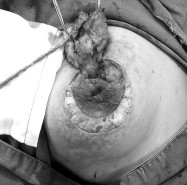

哺乳期发生的乳腺炎女性朋友比较熟悉,经过合理的治疗大多可以痊愈。然而,临床中我们经常发现这样一些病人:她们大多已经哺乳数年或数十年,部分存在乳头内陷畸形,起初乳晕及周围发生局部疼痛性肿块,可伴局部红肿,抗炎治疗效果差,病变进一步发展可以起局部脓肿,破溃或切开后经久不愈,反复发作,甚至肿块范围扩大、引起乳房多发溃烂(见附图1,2),最终导致乳房形态毁损,病程长达数年甚至十余年。这种疾病严重影响了女性朋友的正常生活、异常痛苦,虽为良性疾病,有的患者甚至产生了切除乳房的想法,严重影响了女性的生活质量。这类疾病,我们称为----非哺乳期乳腺炎。